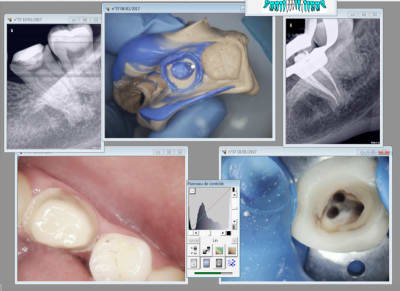

C'est la pulpe c'est la pulpe.

Putain j'ai eu chaud. -) vestibulaire ? Lingual ? vestibulaire lingual ?........Lingual !

Capture d écran 2017 02 20 16.51 - Eugenol

Capture d écran 2017 02 20 17.06 - Eugenol

Il y a un truc bizarre, sur tes RX on a l'impression que l'orifice du canal est distalisé,un peu comme la lésion apicale et ton obturation et plus dans l'axe, un artefact probablement.